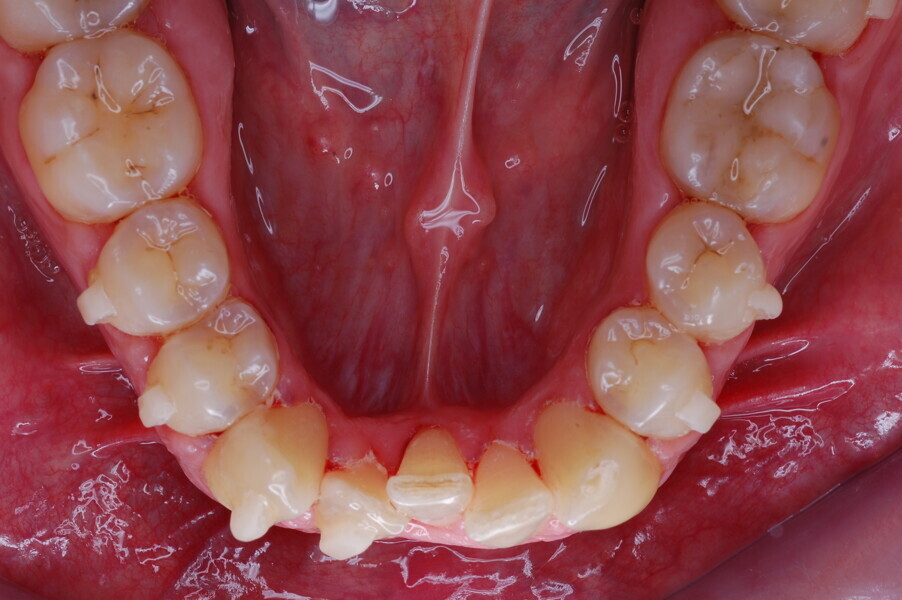

A healthy 39-year-old man presented to our orthodontic office with the chief complaint of an unattractive dental appearance and fear of the orthognathic surgery proposed by another orthodontist. Clinically, the patient’s profile was straight, and the frontal view did not show any facial asymmetry. The functional examination did not reveal any mandibular deviation or reduced movements. The patient had no joint pain, and no joint noise was observed.

Figs. 1–8: Pretreatment facial and intra-oral photographs.

From the periodontal point of view, the patient showed a good attitude to oral hygiene, but crowding of the mandibular incisors made cleaning difficult in that area, causing plaque accumulation and localised gingival inflammation. The panoramic radiograph revealed the presence of the mandibular third molars and confirmed the absence of the mandibular right central incisor (Fig. 10).

The cephalometric analysis showed a skeletal Class II malocclusion (convexity of Point A: 4.9 mm), a slightly retruded chin position (facial depth: 78.1°) and a skeletal open bite tendency (lower facial height: 53.19°; facial axis: 80.58°; Fig. 9). The mandibular incisors were lingually tipped (Li–APog: 9.3°) and retruded (Li–APog: 1.55 mm), and there was an increased inter-incisal angle of 142.9°.